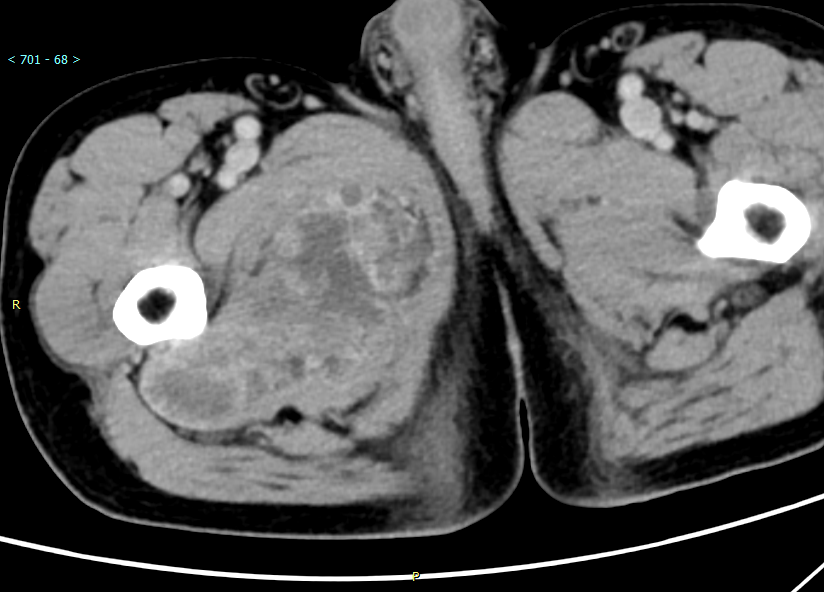

CT平扫

CT平扫 CT+增强

CT所见:右大腿上段内侧肌间隙见不规则肿块影,CT呈低密度影,增强扫描肿块实性部分及纤维分隔明显强化,呈蜂窝状。

CT: 显示与邻近肌肉相比等或低密度肿块,中心区域的密度低于周围,增强扫描实性成分可有轻到中度强化。这些表现与肿瘤的组织学结构相关,肿瘤周围大量的肿瘤细胞呈丝带状和轮辐状,而中央区域黏液基质丰富,肿瘤细胞较少,血管生成很少。CT 扫描对钙化的显示优于磁共振,肿瘤钙化可呈斑点或斑片状。